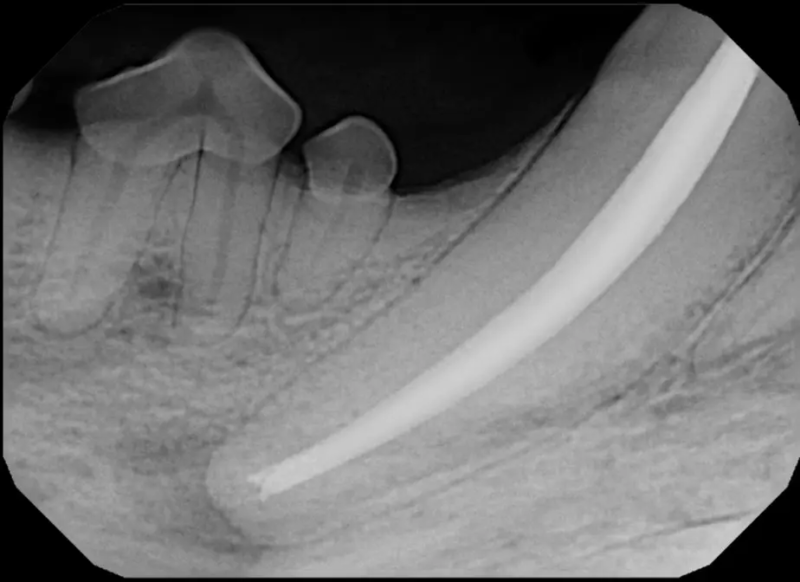

Challenging Extractions

Sometimes teeth can be quite a challenge to remove. We routinely perform difficult extractions due to abnormally formed teeth, impacted teeth, extractions from weakened bone, and retained roots, Sometimes during a routine extraction a root can get pushed into the mandibular canal or the nasal cavity, and if that happens, we are here to get it out!